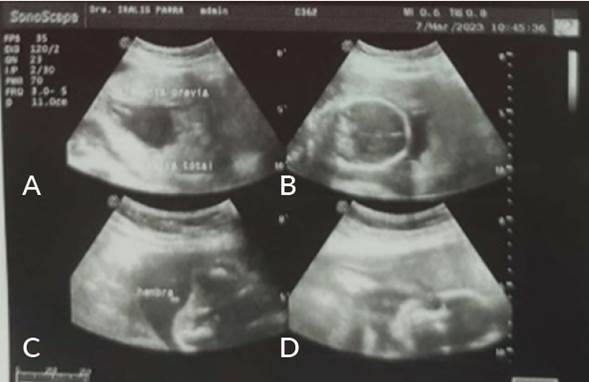

Figura 2 Reporte ecográfico de la paciente a las 23 semanas de gestación (07/03/2023). A: Corte longitudinal. Borde placentario que cubre el orificio cervical interno. B: Corte coronal a nivel del cerebelo. Cráneo fetal en contacto con placenta oclusiva total. C: Corte axial de porción caudal del feto donde se evidencia signo de la hamburguesa (sugestivo de sexo femenino). D: Corte coronal de la cabeza fetal en contacto con la placenta.